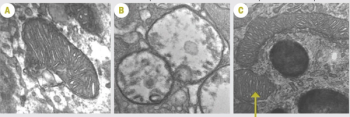

Studying zebrafish helps unravel mysteries of photoreceptor regeneration .